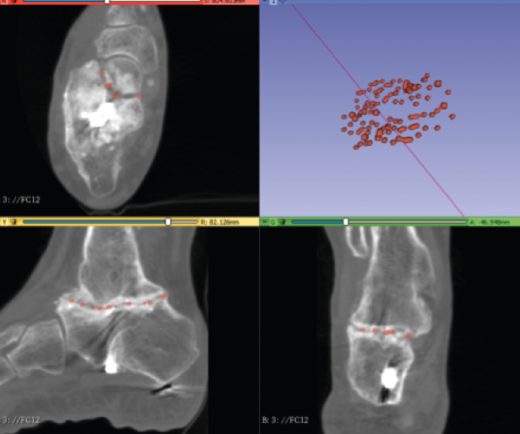

Caso 3. Pseudoartrosis subastragalina

Se trata de un caso del Dr. Cuervas-Mons, publicado en Techniques in Orthopedics(15), acerca de un paciente varón de 54 años que acude a la consulta con dolor del retropié y deformidad en varo. Tras la valoración, se evidencia pseudoartrosis sintomática (Figura 9), por lo que se decide llevar a cabo tratamiento quirúrgico.

Se presenta un problema: la identificación del plano de pseudoartrosis es fácil de manera preoperatoria con el uso de imágenes; sin embargo, la identificación del plano de pseudoartrosis completo de manera intraoperatoria puede ser difícil, siendo necesario una resección ósea amplia y en ocasiones insuficiente.

Utilidad de la impresión 3D: se decidió imprimir una guía 3D de corte como ayuda intraoperatoria. La guía permite la resección de la coalición de manera completa y reducir la necesidad de guía con fluoroscopia.

- Obtención de las imágenes (Figura 10).

- Identificación del plano de pseudoartrosis (Figura 11).

- Diseño de la guía de corte guiada por aguja de Kirschner (Figura 12).